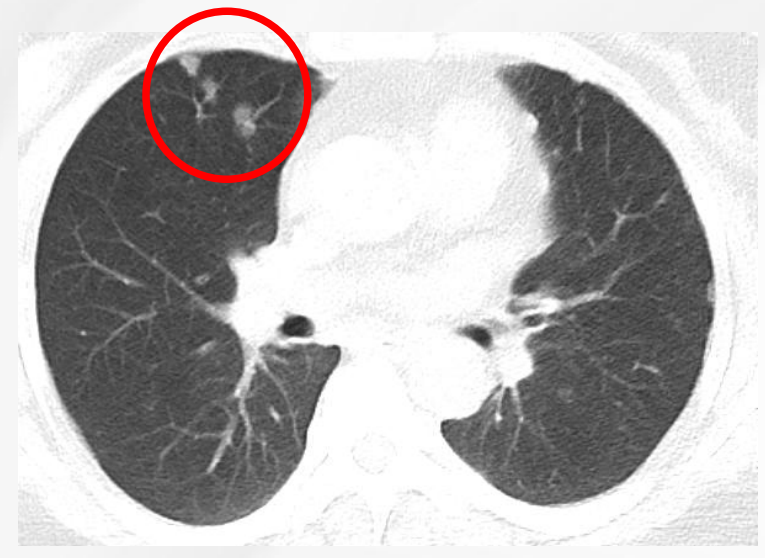

患者为女性,60岁,已绝经,既往史无特殊。2021年5月10日于院内行乳腺及淋巴结彩超检查,提示右乳腺实性结节(BI-RADS 4C级)及右腋下肿大淋巴结。进一步影像学评估显示,右乳原发灶大小约2.7×2.3 cm,右腋窝淋巴结约1.8×1.3 cm;同时可见双肺结节,最大约0.9×0.7 cm,并见右肺门淋巴结约1.1×1.0 cm。整体影像学结果提示患者初诊时已存在乳腺原发灶伴区域淋巴结及肺部转移。

图4:右肺门淋巴结

治疗2个月后影像学复查结果示:右乳腺原发灶由2.7 × 2.3 cm缩小至2.4 × 2.1 cm;右腋窝淋巴结由1.8 × 1.3 cm缩小至1.3 × 0.9 cm;右肺中叶结节由0.9 × 0.7 cm缩小至0.7 × 0.6 cm;右肺门淋巴结由1.1 × 1.0 cm缩小至1.0 × 0.9 cm。本次复查显示乳腺原发灶缩小11%腋窝淋巴结、肺病灶、右肺门淋巴结均缩小。总体疗效评估为疾病稳定(SD)。这提示患者在治疗早期即出现客观影像学改善,但尚未达到部分缓解(PR)阈值。

治疗12个月后,患者疗效进一步加深。右乳腺原发灶缩小至1.2 × 0.9 cm;右腋窝淋巴结缩小至0.5 × 0.3 cm;右肺中叶原结节影未再显示;右肺门淋巴结缩小至1.0 × 0.4 cm。本次复查显示乳腺原发灶缩小56%;同时腋窝淋巴结、肺病灶及右肺门淋巴结均达到影像学CR,整体疗效由早期SD进一步转化为PR。对晚期HR+/HER2-乳腺癌而言,这种由初期肿瘤控制向持续缓解的演变,具有较强的临床意义。

截至治疗4年6个月时,患者仍维持持续获益。右乳腺原发灶缩小至0.6 × 0.5 cm;右腋窝淋巴结缩小至0.4 × 0.3 cm;右肺中叶原结节影未再显示;右肺门淋巴结缩小至0.7 × 0.4 cm。本次复查显示乳腺原发灶缩小78%;腋窝淋巴结、肺病灶、右肺门淋巴结影像学CR。总体疗效评估为持续PR。